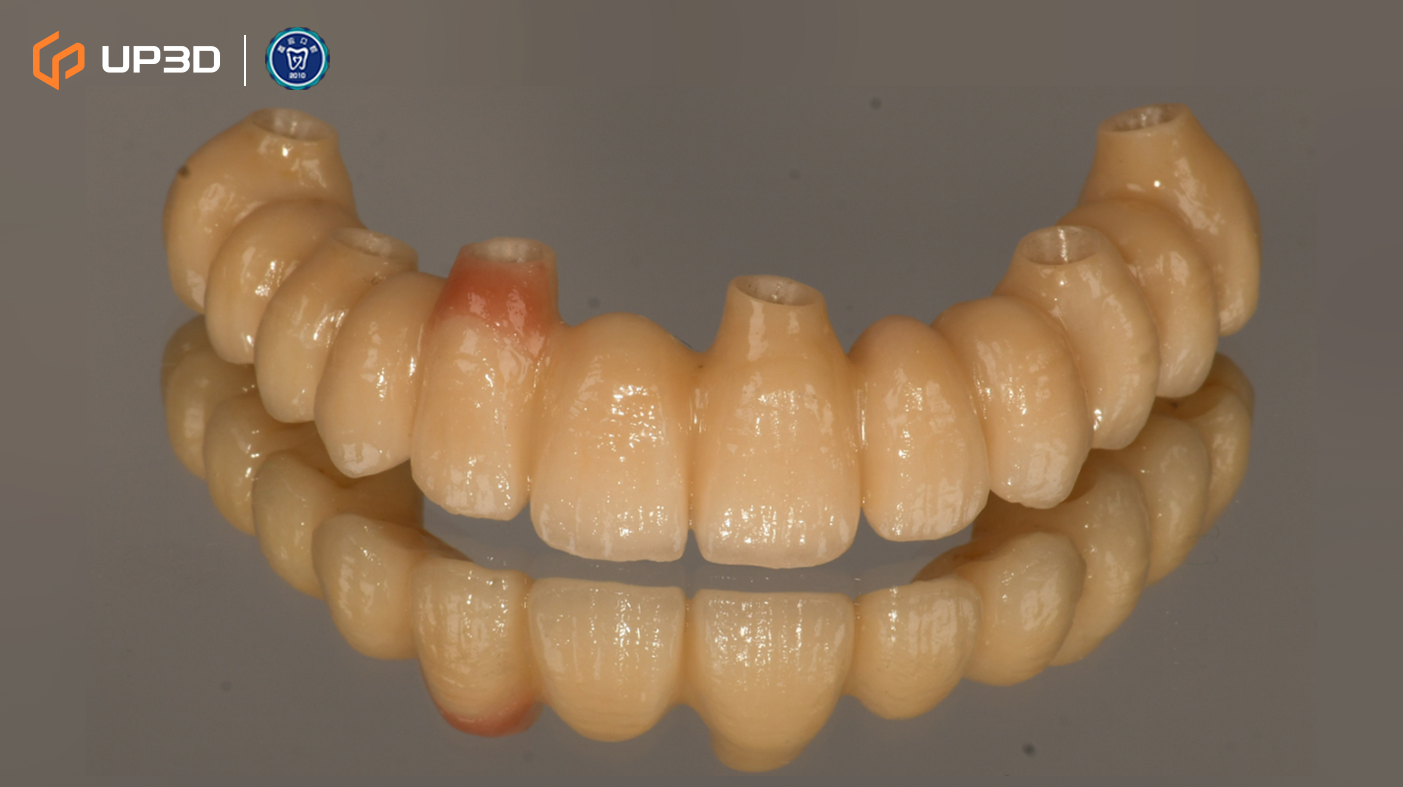

7.3 Chairside Milling of the Zirconia Restoration

High-strength zirconia was selected for chairside fabrication. Milling was performed using the UP3D P55D. The definitive restorations showed:

-

Clean, well-defined margins that supported accurate seating

Stable surface quality and consistent milling results

High fidelity in anatomical morphology and occlusal detail reproduction—helping reduce chairside adjustments and minimizing the risk of remakes

The zirconia restorations were completed within approximately 48 hours, enabling a timely transition into final delivery.